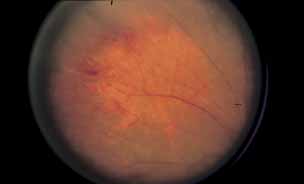

Fig. 4 Luetic neuroretinitis. Color photograph showing placoid opacity at the level of the retinal pigment epithelium.

Fig. 5 Luetic neuroretinitis. A late frame of the angiogram in Figure 4 shows extensive staining of the entire area corresponding to leakage into the outer retina and staining of the pigment epithelium. The patient was successfully treated with intravenous penicillin therapy and subsequently developed diffuse “leopard spot” changes in the pigment epithelium characteristic of resolved luetic neuroretinitis.